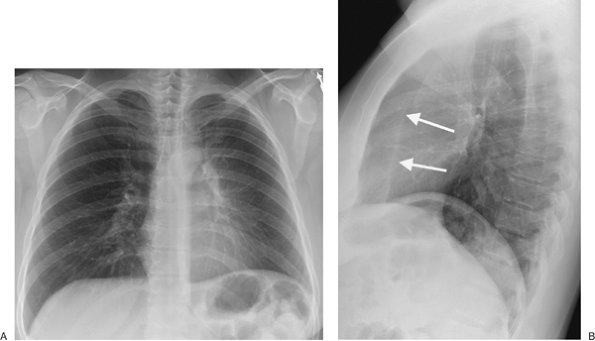

FIGURE 11-17. Left upper lobe collapse. A: PA chest radiograph of a 44-year-old man with a 6-month history of recurrent pneumonia shows elevation of the left hemidiaphragm, hazy opacity of the left hemithorax, and loss of the left heart border. B: Lateral view shows anterior displacement of the left major fissure (arrows) and increased retrosternal opacity. Bronchoscopic biopsy of a left upper lobe endobronchial mass confirmed the diagnosis of a bronchial carcinoid tumor as the cause of the left upper lobe collapse.